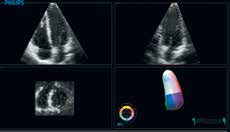

EPIQ 7C高端超声系统支持全面的具创新性的探头。只需一键按钮xMATRIX即可提供单探头的全模式应用:二维,M型,彩色多普勒,多普勒,iRotate智能旋转,实时二维切面,实时三维,实时三维缩放,及全容积实时三维。

nSIGHT使得强大的xMATRIX技术如虎添翼

使用实时任意多平面xPLANE同时创建多个全像素分辨率平面,让您在同一时间获得多倍临床信息。在全容积成像内以立方体素的分辨率来显示任何平面的图像。现在,一切都成为可能。

X5-1纯净波矩阵探头对二维、三维实时图像清晰度的体现。

纯净波矩阵探头还包括支持儿童三维成像的X7-2和支持3DTEE应用的X7-2t